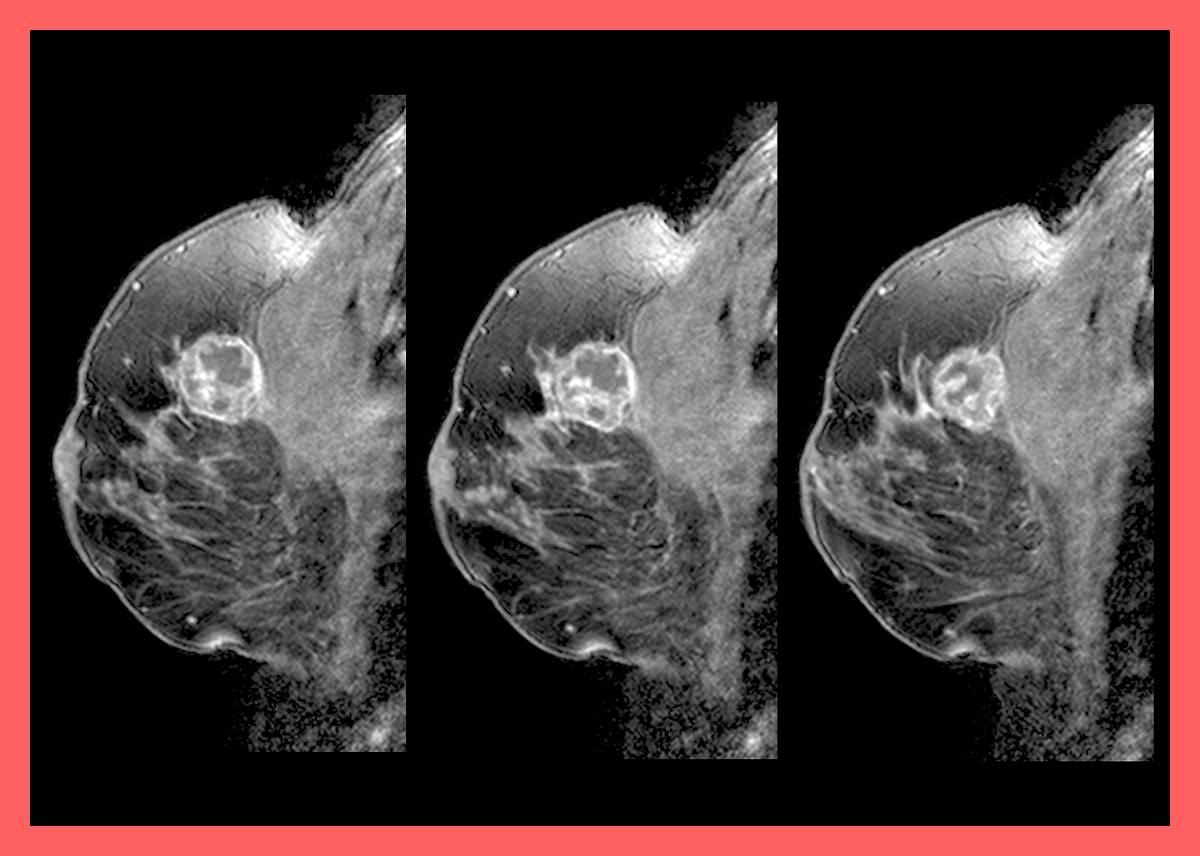

유방암 초기증상

유방암 초기증상 1.유방 멍울(응어리)

유방암 발병자의 90% 정도 멍울(응어리)이 생기는 것으로 알려져 있습니다. 사람에 따라 느낌이 다를 수 있는데 딱딱한 정도로 응어리가 생긴 것으로 암일 경우 점차 커진다고 합니다. 유방암 초기 증상으로 가장 흔한 정상입니다. 양성 질병으로 인한 것도 매우 많다고 합니다. 양성덩어리는 탄력성이 있어서 움직이는 경향이 있지만 유방암 덩어리는 잘 움직이지 않는다고 합니다.